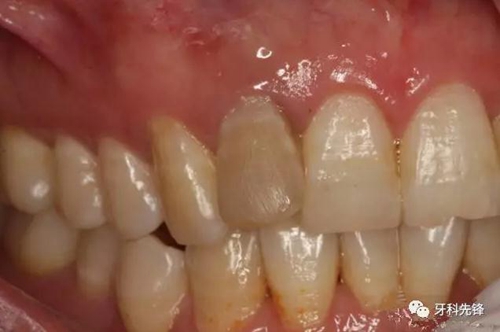

圖2.12牙冠成灰褐色,唇側(cè)粘膜正常。